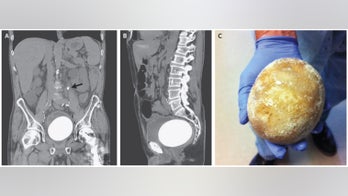

DIGESTIVE HEALTH September 14, 2017 Man's bladder stone was almost as big as an ostrich egg When a man in California went to the hospital because of bladder problems, doctors found a large reason for his pain: a mineral stone nearly the size of an ostrich egg, according to a new report of the case.